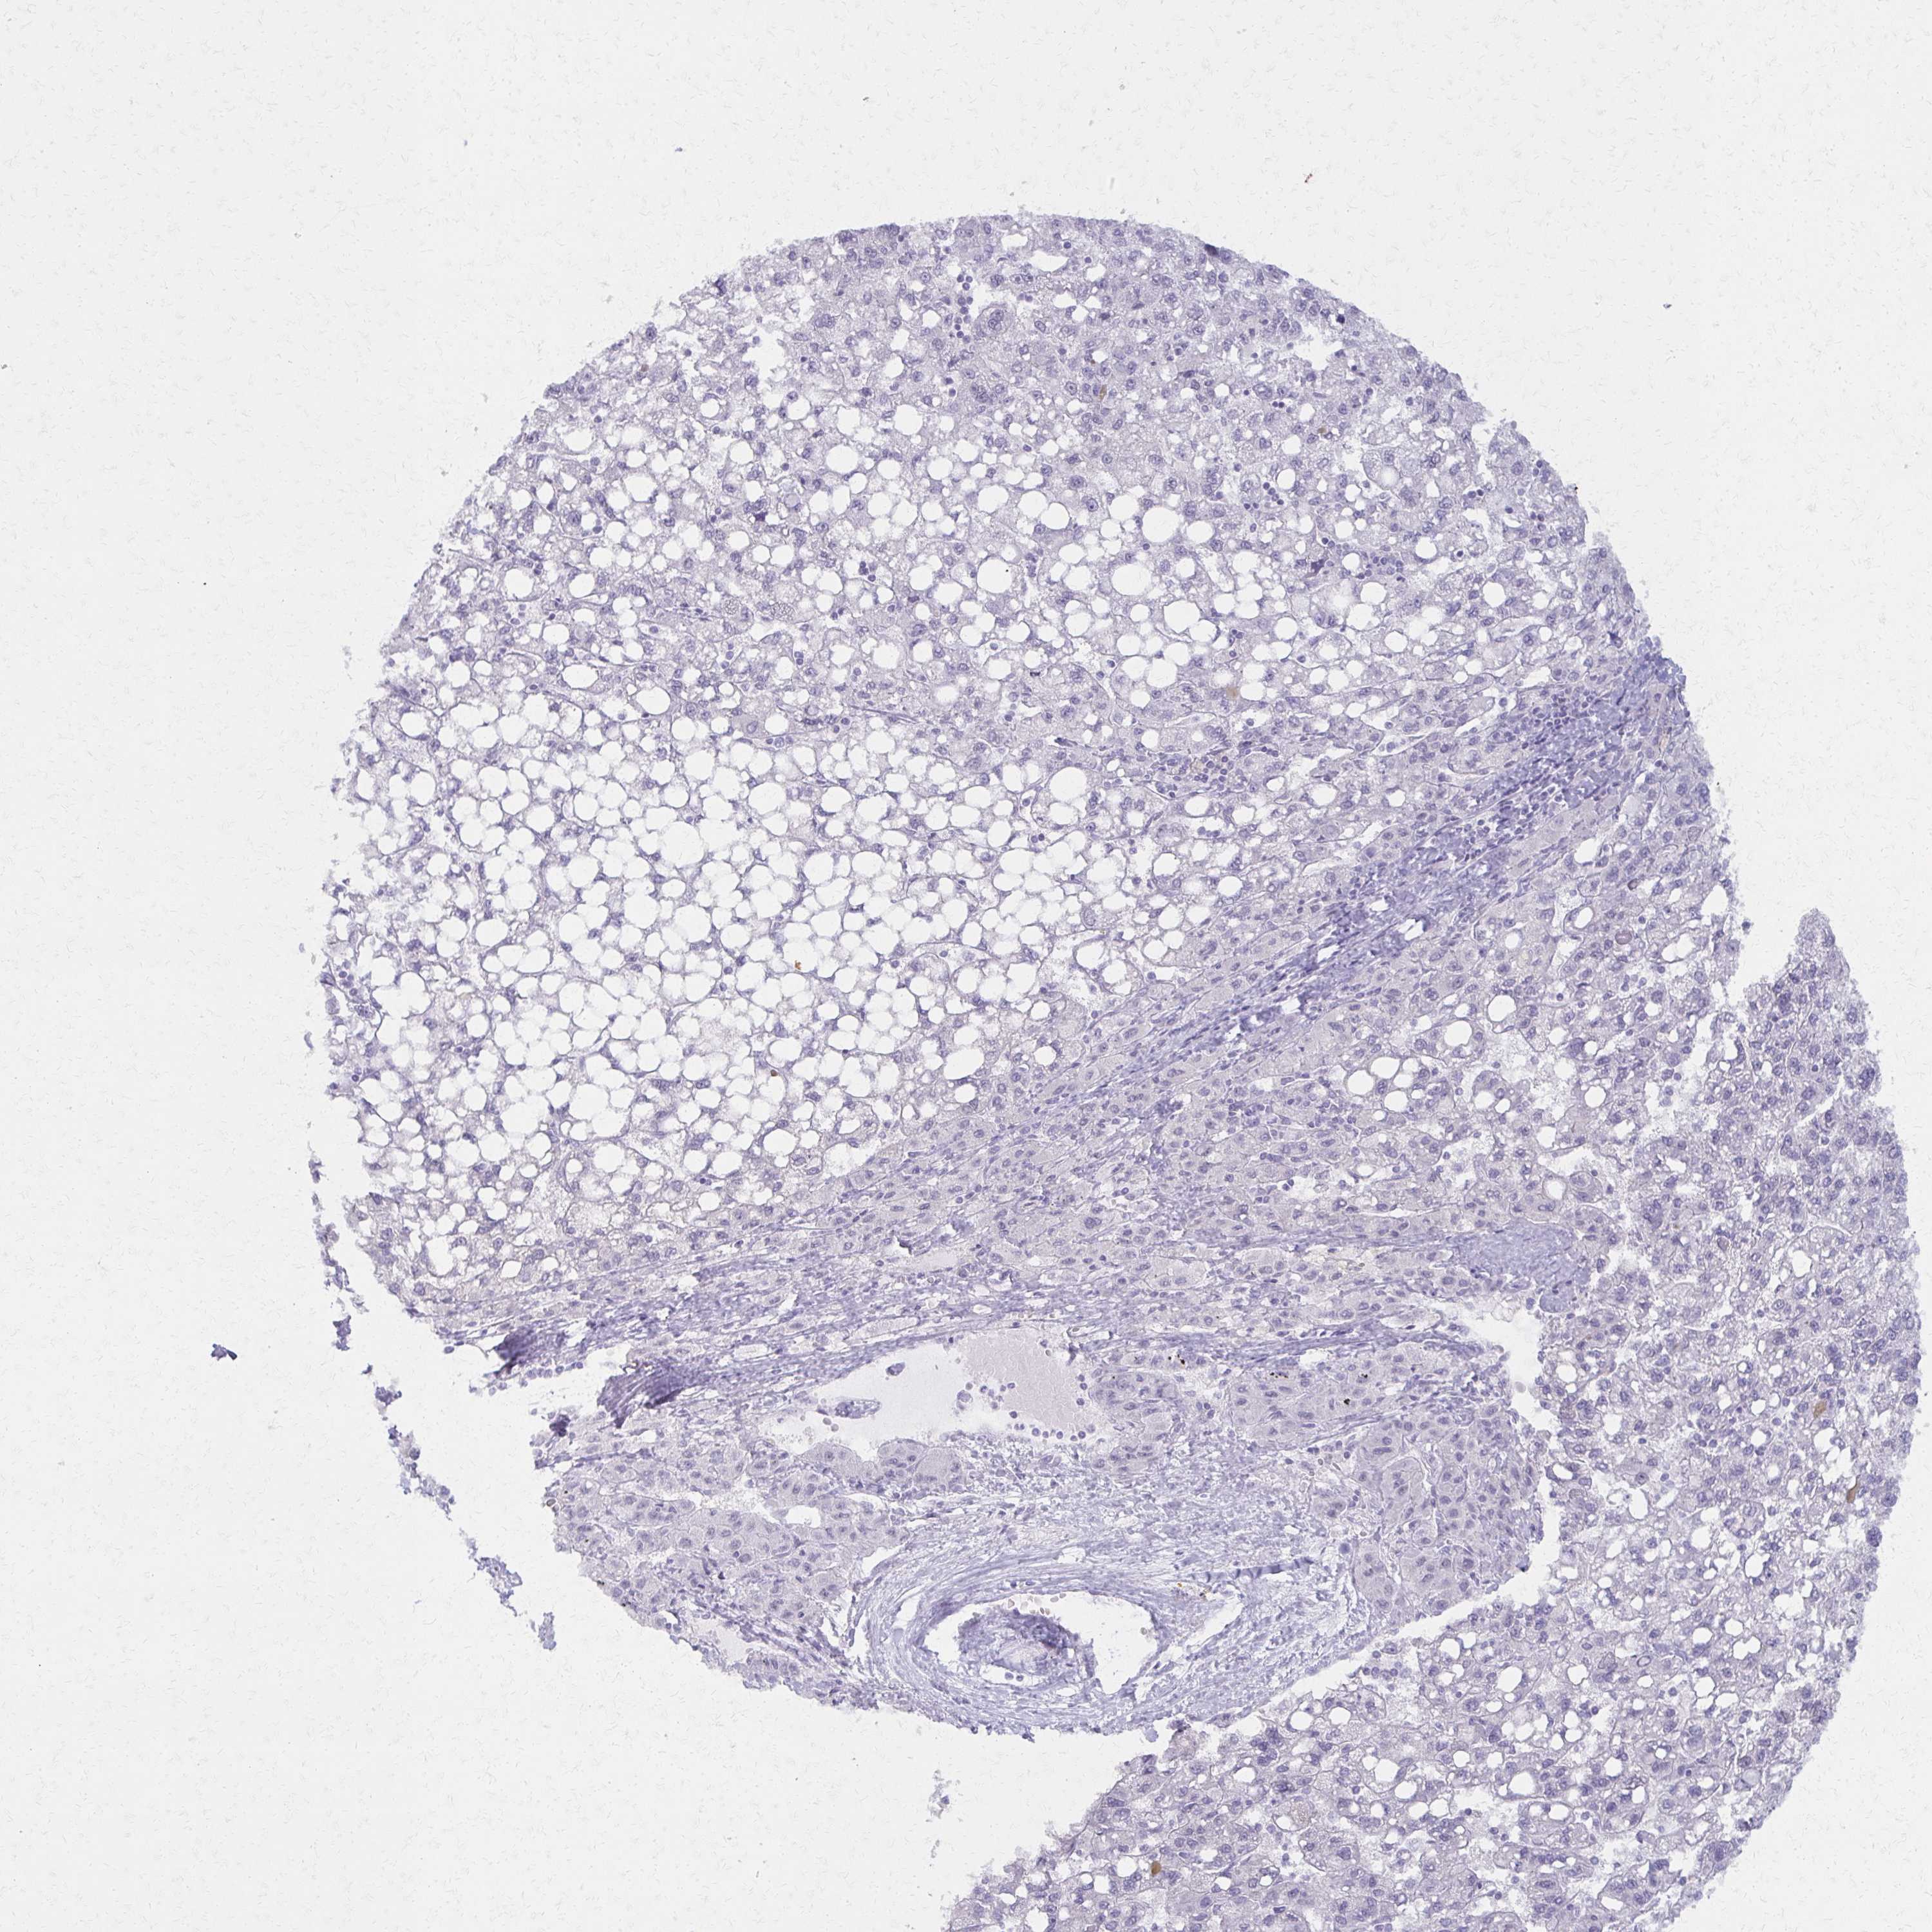

LIVER CANCER - Protein expressioni

A mouse-over function shows sample information and annotation data. Click on an image to view it in a full screen mode. Samples can be filtered based on level of antibody staining by selecting one or several of the following categories: high, medium, low and not detected. The assay and annotation is described here.

Note that samples used for immunohistochemistry by the Human Protein Atlas do not correspond to samples in the TCGA dataset.

Antibody stainingi

Antibody staining in the annotated cell types in the current human tissue is reported as not detected, low, medium, or high, based on conventional immunohistochemistry profiling in selected tissues. This score is based on the combination of the staining intensity and fraction of stained cells.

Each image is clickable and will lead to virtual microscopy that enables deeper exploration of all samples and also displays staining intensity scores, fraction scores and subcellular localization as well as patient and tissue information for each sample.

Antibody HPA000395

Antibody HPA015547

Staining

High

Medium

Low

Not detected

Intensity

Strong

Moderate

Weak

Negative

Quantity

>75%

75%-25%

<25%

None

Location

Nuclear

Cytoplasmic/membranous

Cytoplasmic/membranous,nuclear

Carcinoma, Hepatocellular, NOS

Cholangiocarcinoma